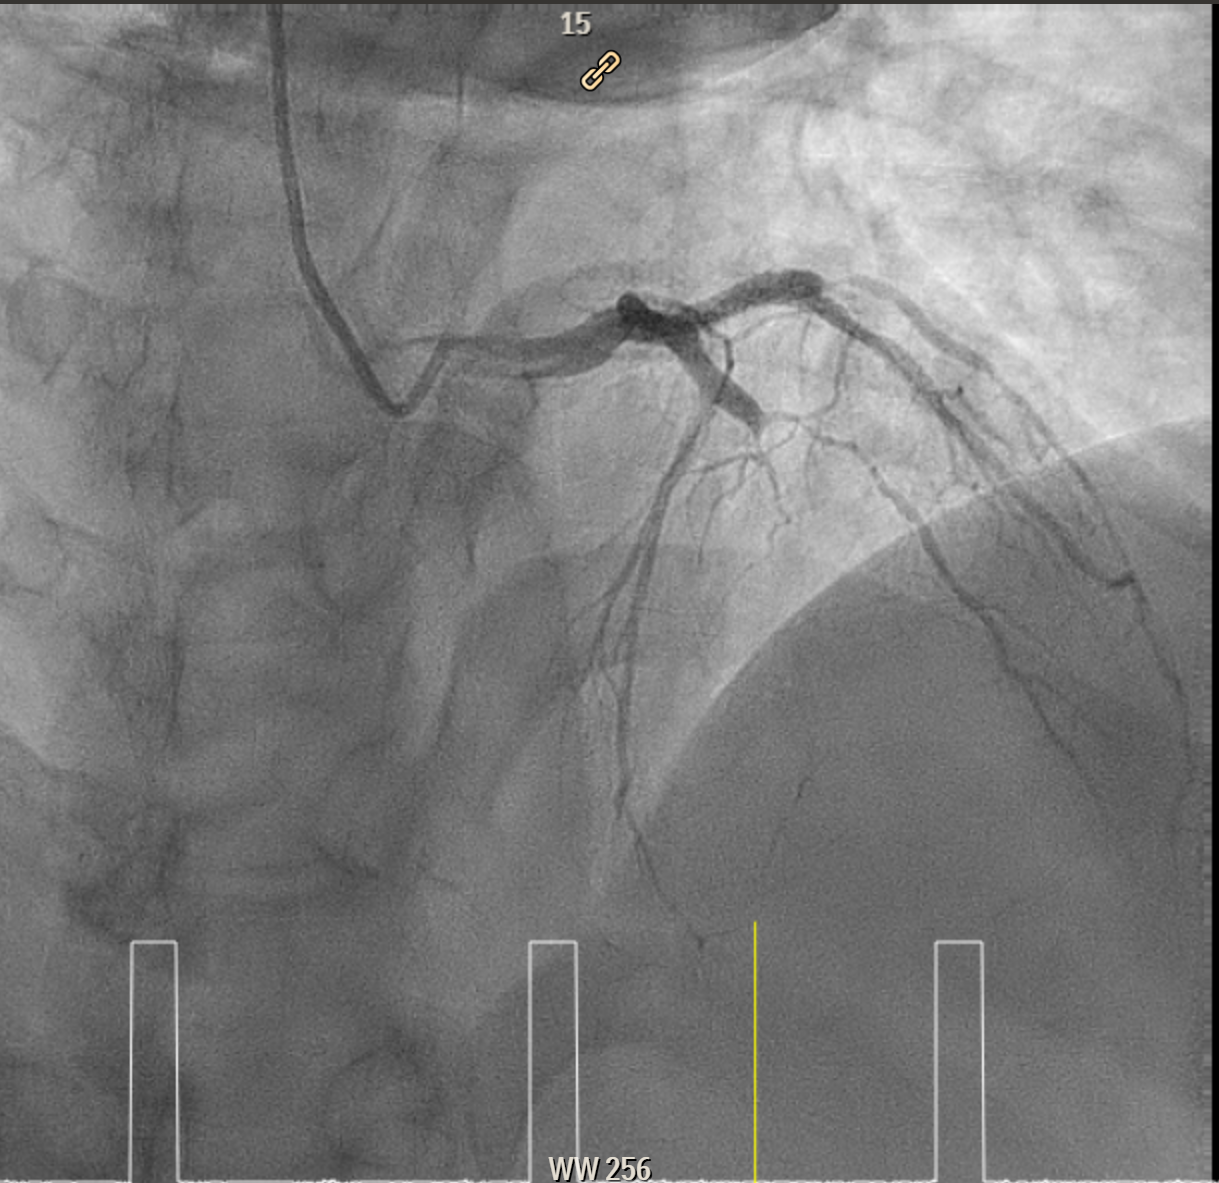

Elective angiogram was performed 3 months later as he declined procedure during index admission. Coronary angiogram showed total occlusion of proximal LAD at bifurcation of first diagonal and first septal branches. It received collateral supply from conus branch and first septal branch (Rentrop 2). J-CTO score was 2, and PROGRESS-CTO score was 1, indicate moderate complexity. Additionally, RCA was huge and dominant, while proximal first OM branch of LCX was 80–90% diseased.